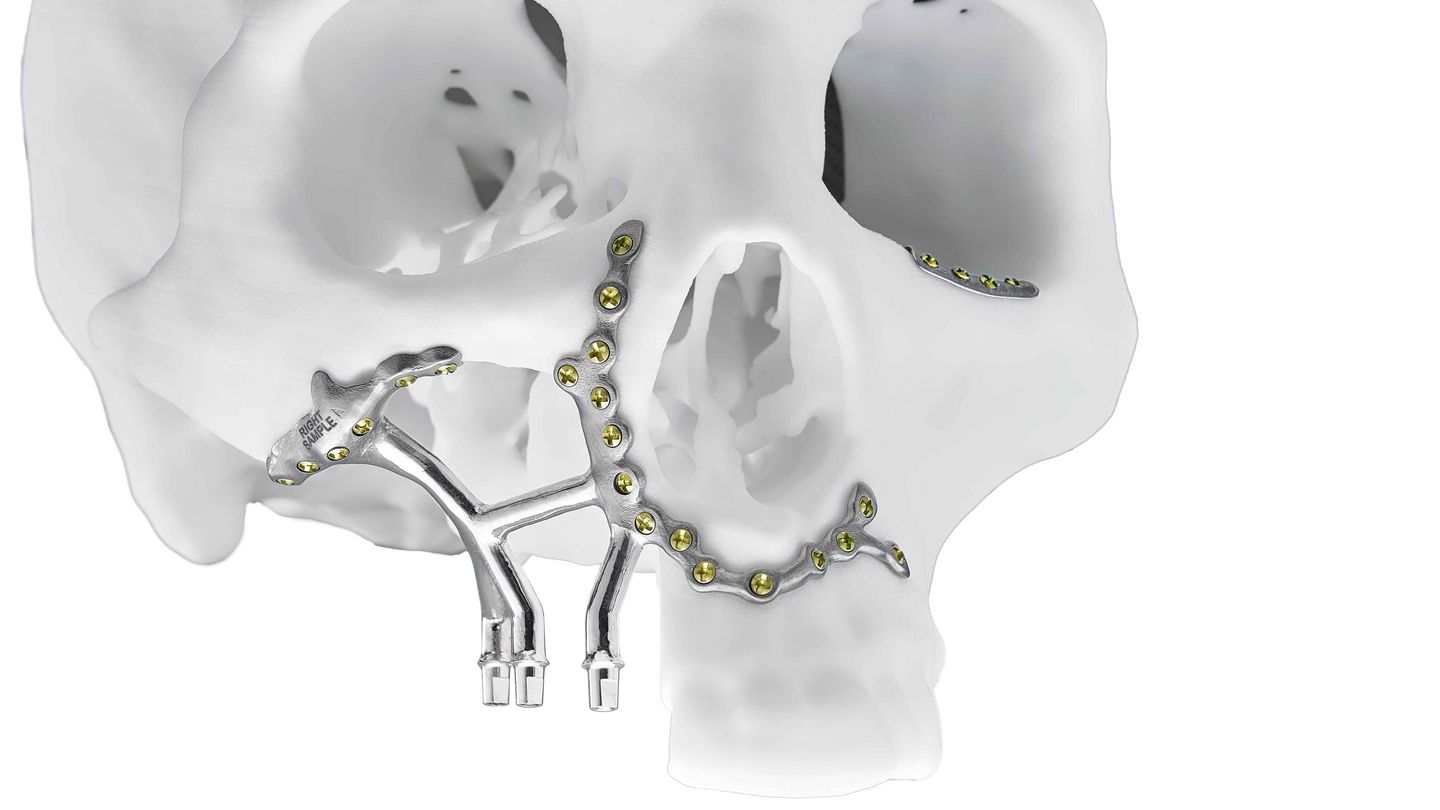

Additive manufacturing enables the patient's anatomy to be reconstructed without bone augmentation. This means fewer surgical procedures and therefore less stress for the patient.

Examples of personalised implants in oral and maxillofacial surgery

- Component dimensions: Jaw implant: 176 mm x 94 mm x 135 mm, Pre-prosthetic implant: 55 mm x 55 mm x 55 mm, Orbital implant: 41 mm x 18 mm x 34 mm

- Weight: Jaw implant: 113 g, Pre-prosthetic implant: 10 g, Orbital implant: 1 g

- Volume: Jaw implant: 25.5 cm³, Pre-prosthetic implant: 2.3 cm³, Orbital implant: 0.3 cm³

- Customer: KARL LEIBINGER MEDIZINTECHNIK, a KLS Martin Group company